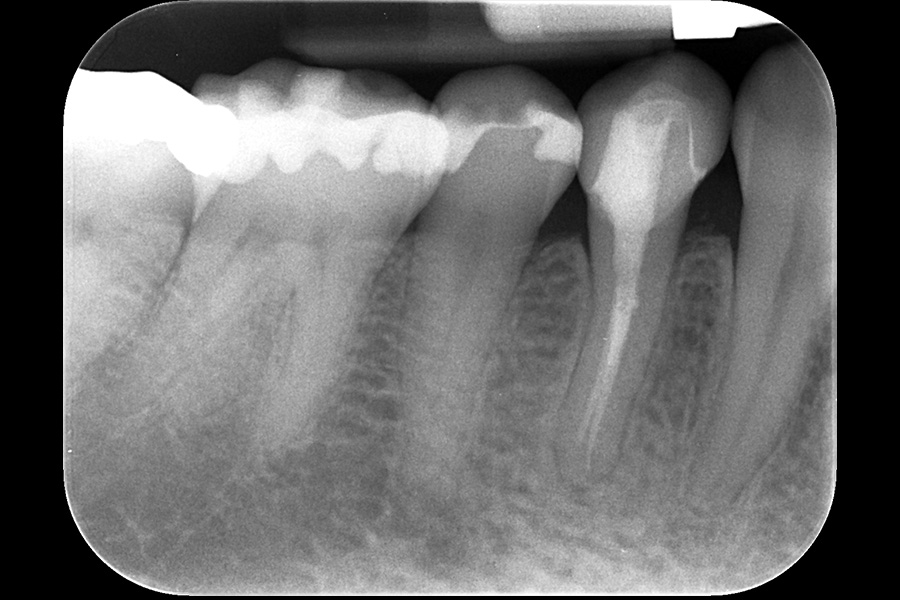

治療前